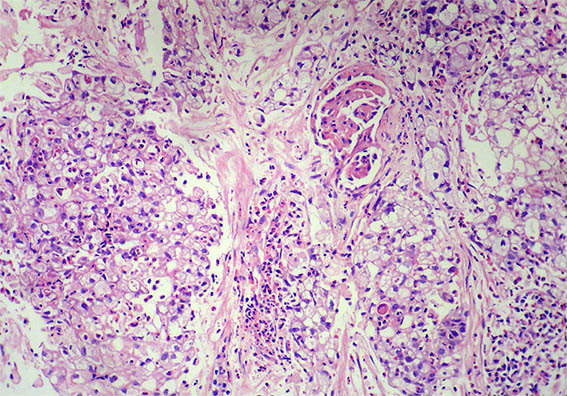

Figura 3.

H&E, X100.